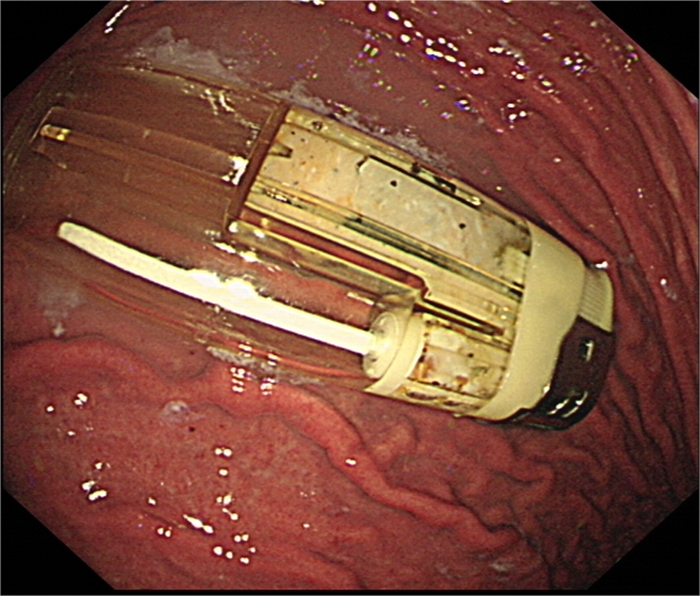

在全麻下電子胃鏡進(jìn)入胃內(nèi),可見1枚完整打火機(jī),考慮到打火機(jī)較大,且邊緣較硬,容易劃傷賁門及食管黏膜,醫(yī)生先使用異物鉗夾住安全套,隨胃鏡進(jìn)入胃內(nèi),將安全套套住打火機(jī),異物鉗夾住安全套開口處,隨胃鏡緩慢取出。后重新進(jìn)鏡觀察,所經(jīng)的賁門粘膜及食管粘膜無明顯損傷,表明異物取出成功。